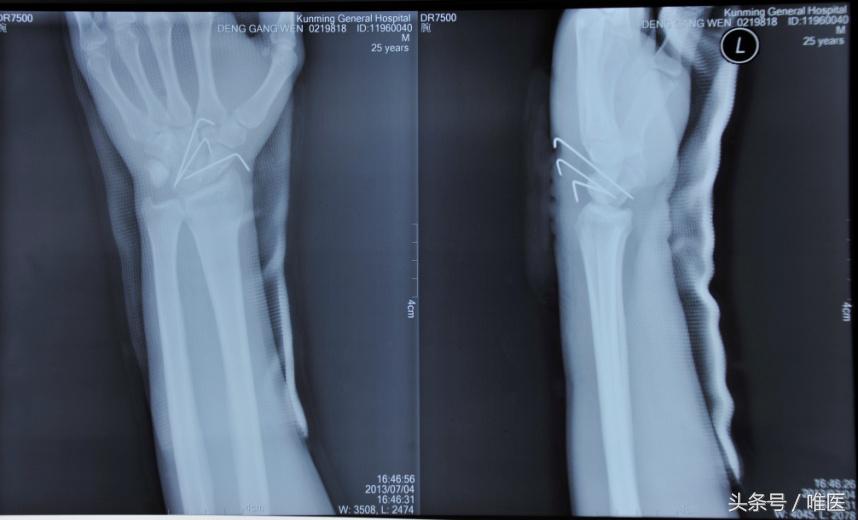

1.克氏针固定锻炼

此方法由于无加压作用骨舟骨易出现骨不连。这是一种较早出现的治疗方法,用2枚克氏针平行或交叉固定舟骨骨折,对于固定时间笔者综合国内外文献总结对于石膏及克氏针固定时间一般不少于6周,多为管型石膏固定3个月,但具体以复查X线视骨折愈合情况决定,拔出克氏针后逐步进行腕关节功能。